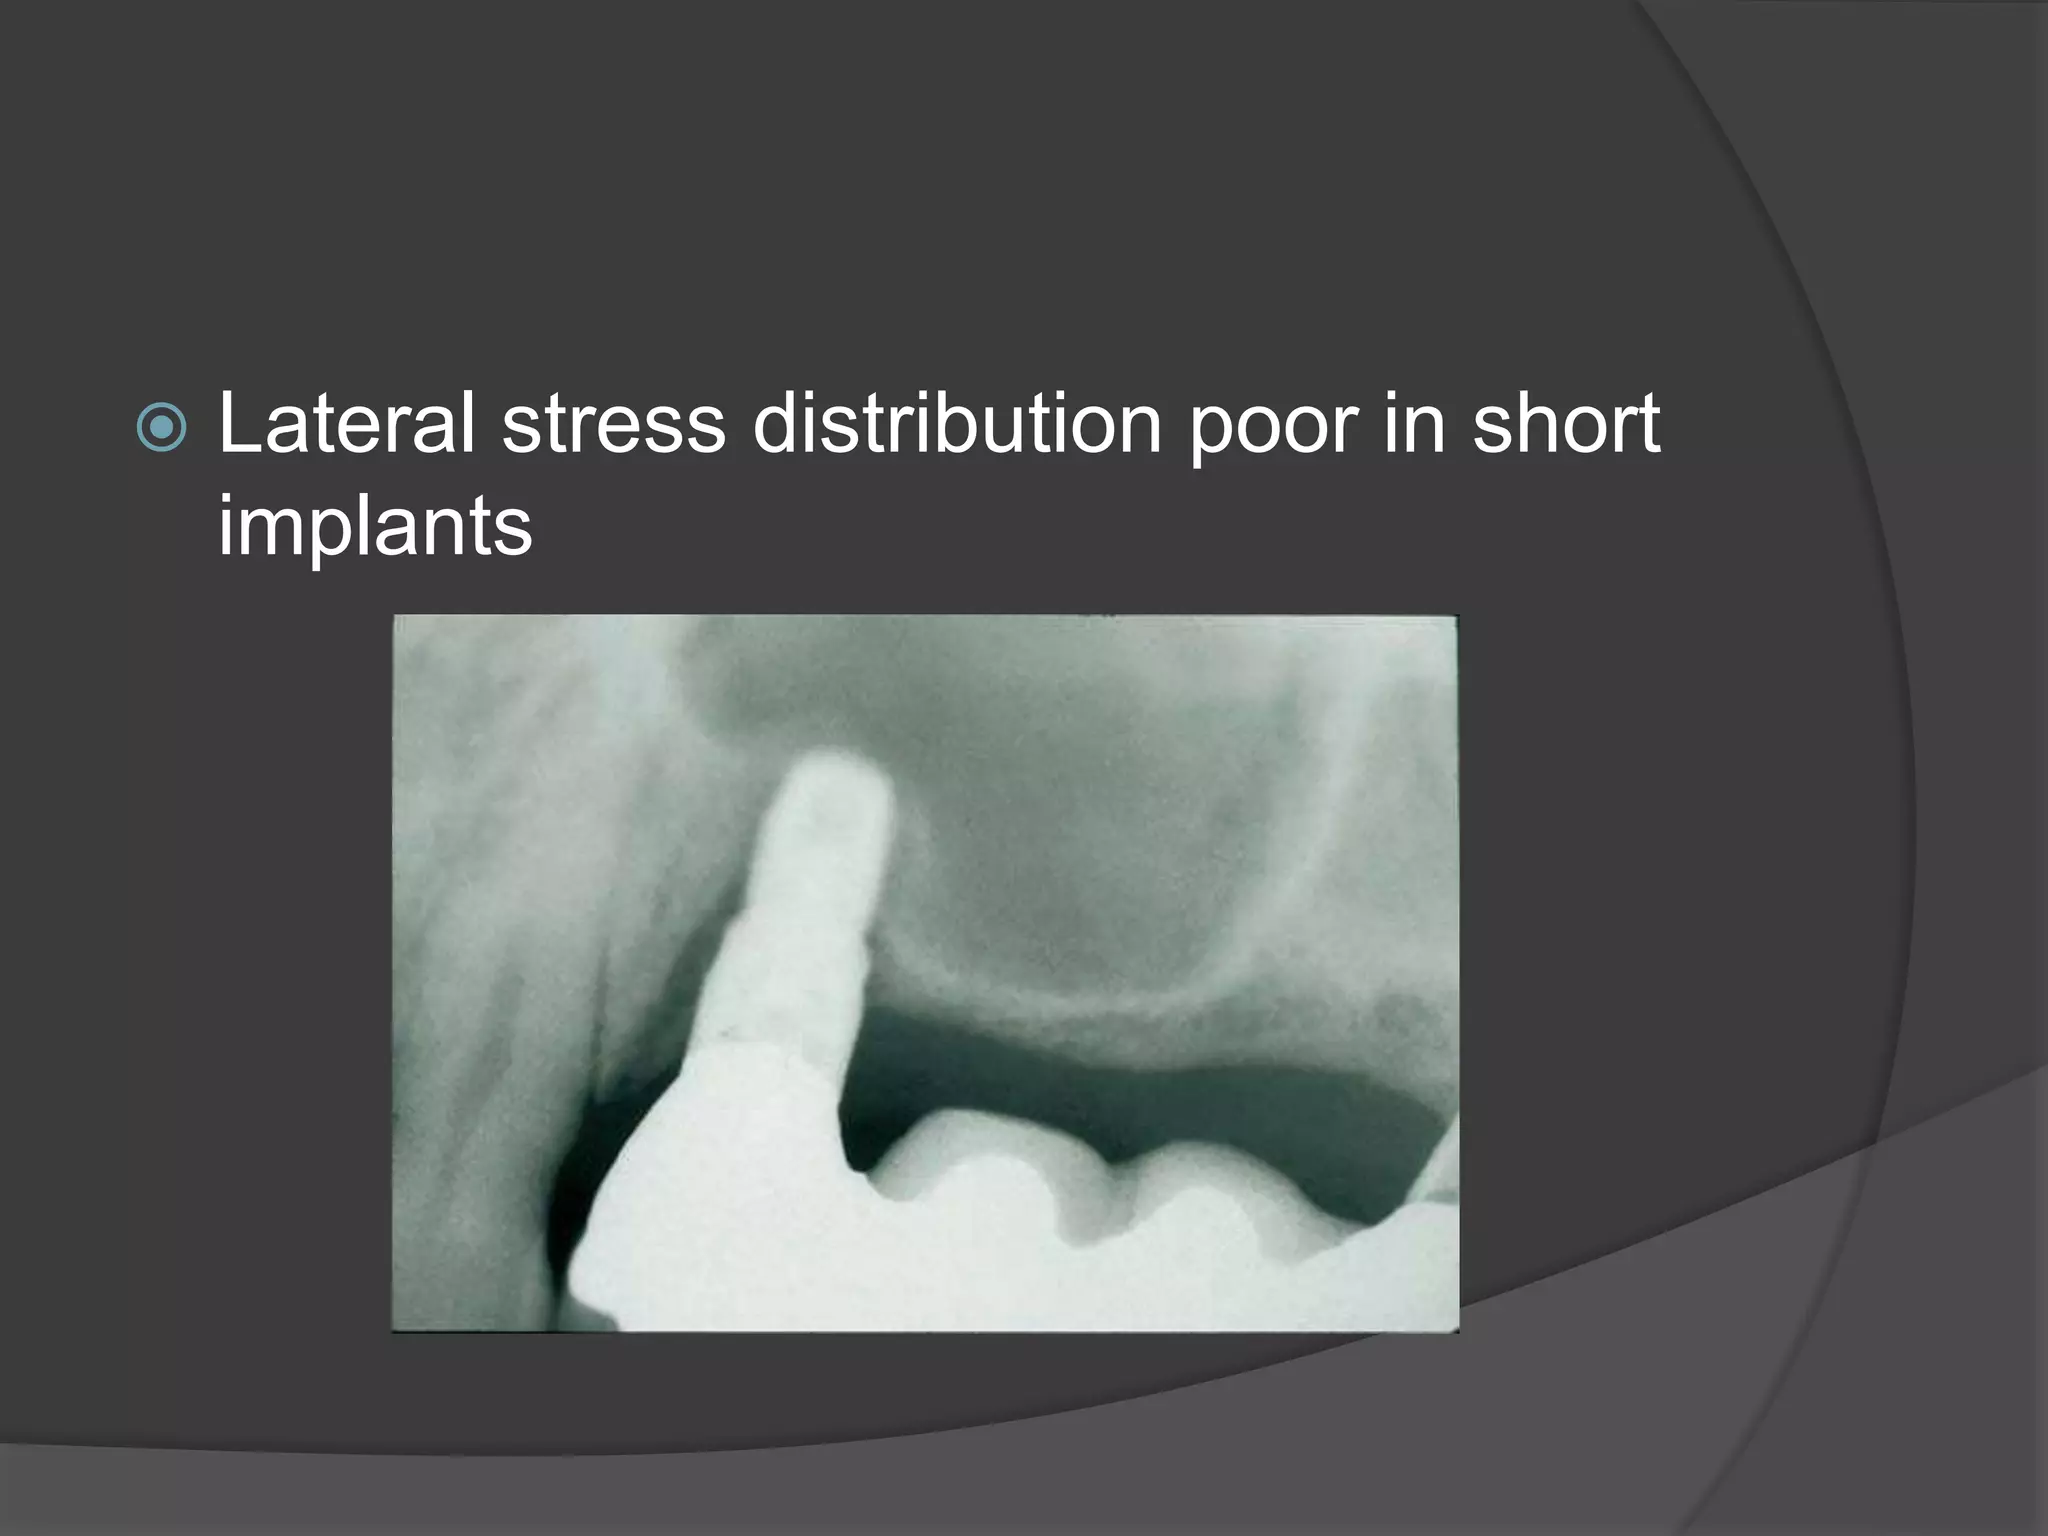

This document discusses factors that influence osseointegration and primary stability of dental implants, including implant design characteristics, surgical technique, and loading protocols. Specifically, it covers the processes of osseointegration and how forces on implants can either promote or inhibit bone remodeling. Key implant design considerations like length, diameter, threads, coatings and surface topography are analyzed in terms of their effects on stress distribution and bone-implant contact. The importance of primary stability and factors influencing it like bone quality and surgical skill are also addressed. Loading protocols ranging from immediate to conventional loading are compared.